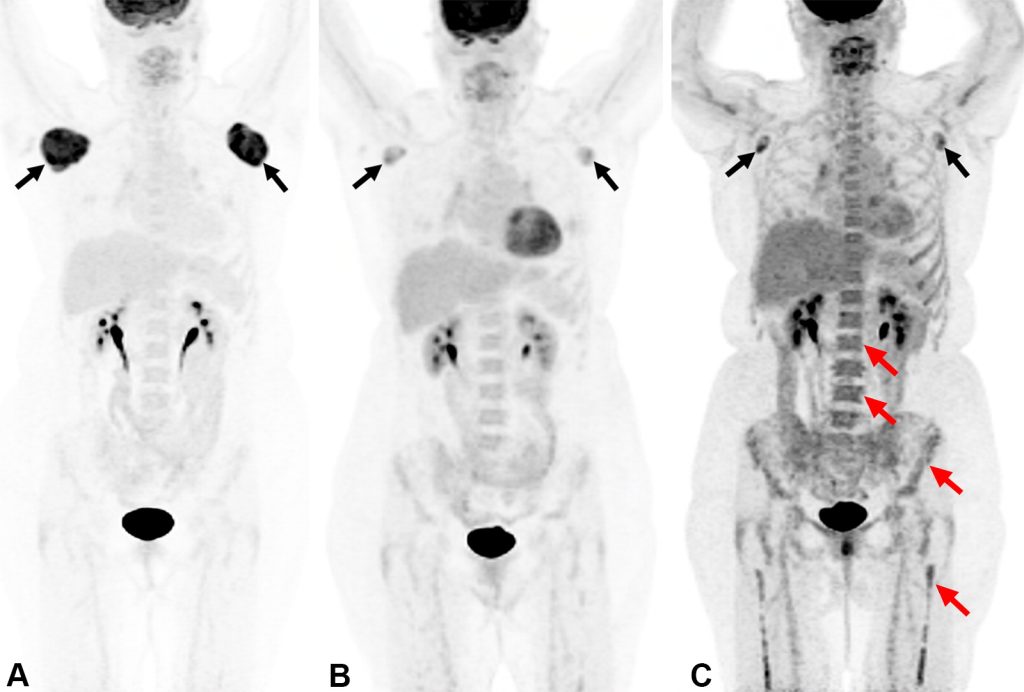

ضایعات بدخیم کبدی و مدیریت آنها: در میان ضایعات بدخیم کبد، کارسینوم هپاتوسلولار (HCC) شایعترین نوع سرطان اولیه کبد است که اغلب در بیماران مبتلا به سیروز یا عفونت مزمن ویروسی کبد دیده میشود. در تصویربرداری CT و